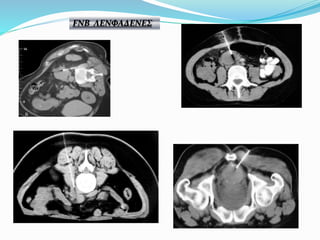

FNB ΛΕΝΦΑΔΕΝΕΣ